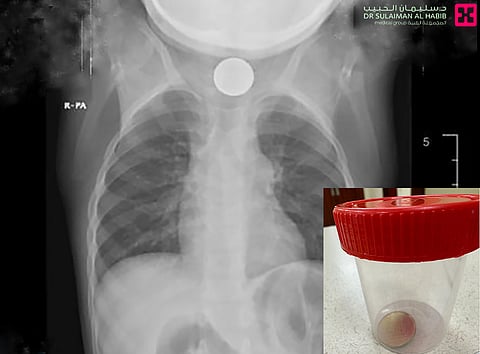

وقال د. توفيق؛ إن الطفلة وصلت الطوارئ وهي تشتكي من استفراغٍ متكرّرٍ مستمرٍ لأيامٍ عدة، ثم تطوّر الأمر لاحقاً، وأُصيبت بنوبات تشنجٍ و"كحة"، فأُسعفت إلى المستشفى، وخضعت فور وصولها إلى عدة فحوص دقيقة، منها صور الأشعة التي بيّنت وجود جسمٍ غريبٍ في البلعوم السفلي، فتواصل الفريق الطبي بالطوارئ مع استشاري جراحة الأنف والأذن والحنجرة، الذي قرّر بعد دراسة الحالة إخضاع الطفلة لعمليةٍ عاجلة باستخدام تقنية المنظار، لكن عند تنظير البلعوم لم يظهر أثرٌ للجسم الغريب، فتم إجراء منظار للمريء، وعُثر على الجسم وهو "عملة معدنية من فئة الـ50 هللة ذهبية اللون"، في الجزء العلوي منه، وتكللت -ولله الحمد- جهود الفريق الطبي بنجاح العملية والتقاط الجسم وإخراجه.